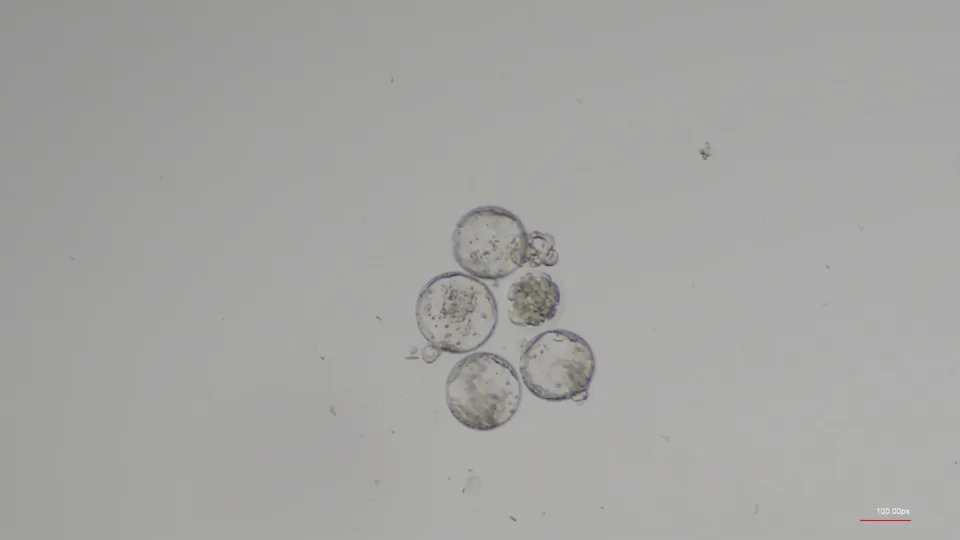

Can humans have babies in space? It may be harder than expected

Images